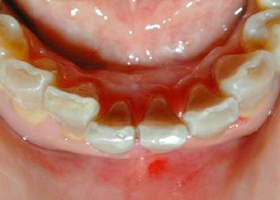

1.術前口內正面照、局部X光片。

2. 上顎明顯暴牙、下顎參差不齊。

3.矯正前,明顯可見暴牙。